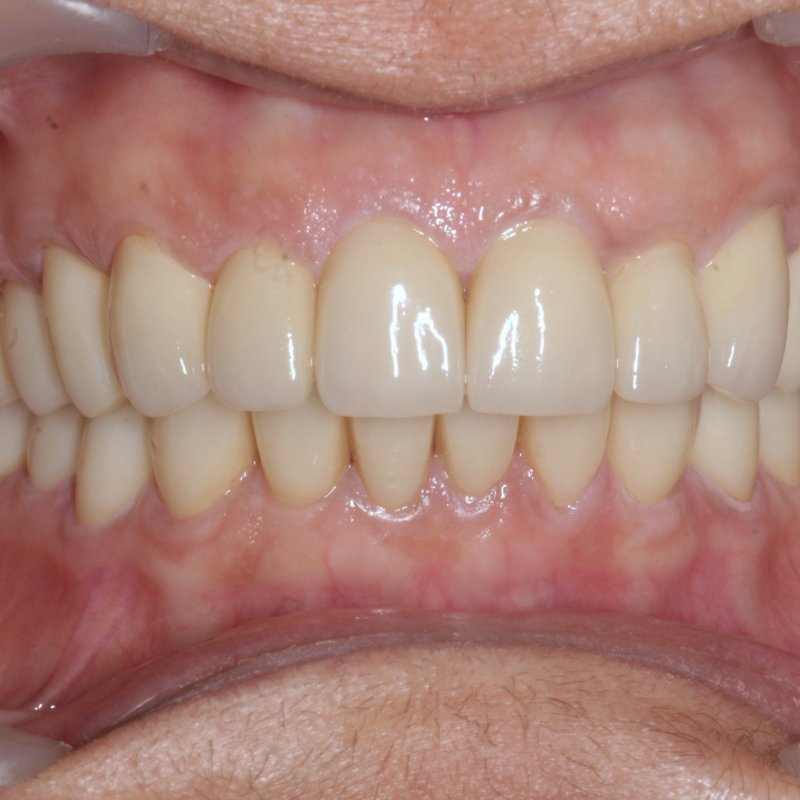

After full mouth rehabilitation

Full Mouth Rehabilitation

Complete reconstruction

Comprehensive restoration combining implants, crowns, and bridges to rebuild a full functional bite and natural-looking smile.